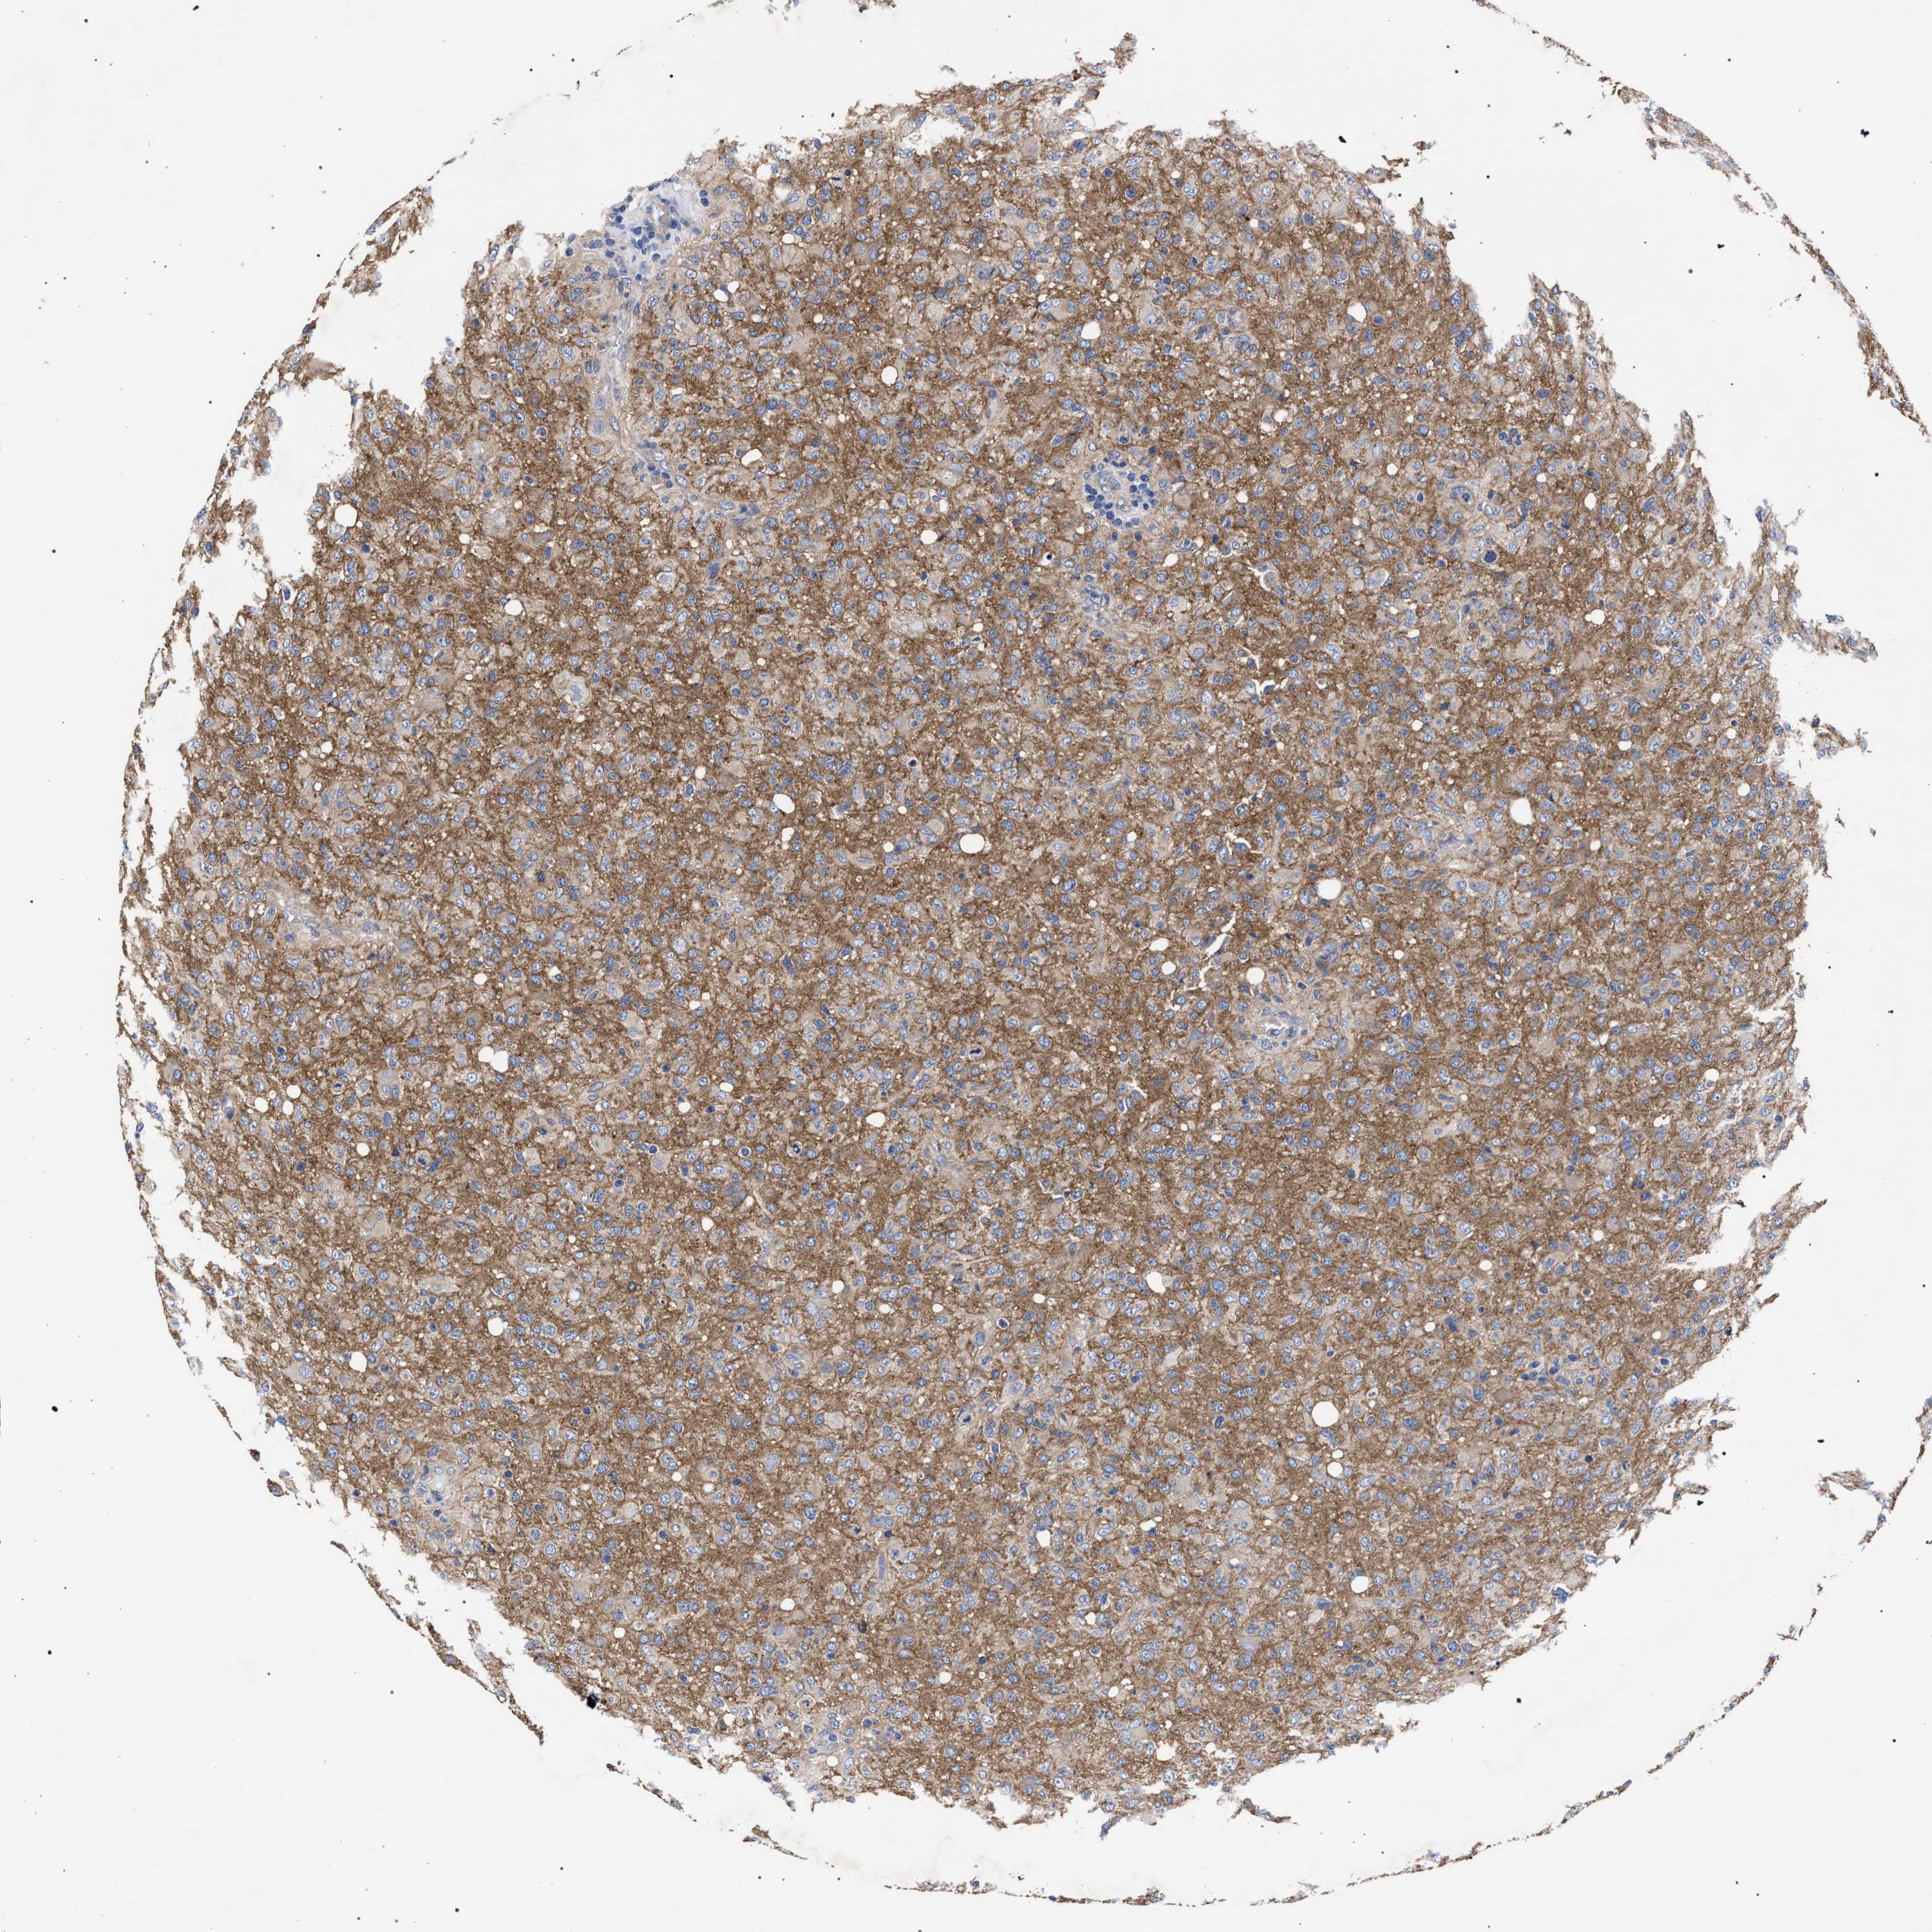

GLIOMA - Protein expressioni

A mouse-over function shows sample information and annotation data. Click on an image to view it in a full screen mode. Samples can be filtered based on level of antibody staining by selecting one or several of the following categories: high, medium, low and not detected. The assay and annotation is described here.

Antibody stainingi

Antibody staining in the annotated cell types in the current human tissue is reported as not detected, low, medium, or high, based on conventional immunohistochemistry profiling in selected tissues. This score is based on the combination of the staining intensity and fraction of stained cells.

Each image is clickable and will lead to virtual microscopy that enables deeper exploration of all samples and also displays staining intensity scores, fraction scores and subcellular localization as well as patient and tissue information for each sample.

Antibody HPA021261

Antibody HPA021325

Staining

High

Medium

Low

Not detected

Intensity

Strong

Moderate

Weak

Negative

Quantity

>75%

75%-25%

<25%

None

Location

Nuclear

Cytoplasmic/membranous

Cytoplasmic/membranous,nuclear

Glioma, malignant, High grade

Glioma, malignant, Low grade